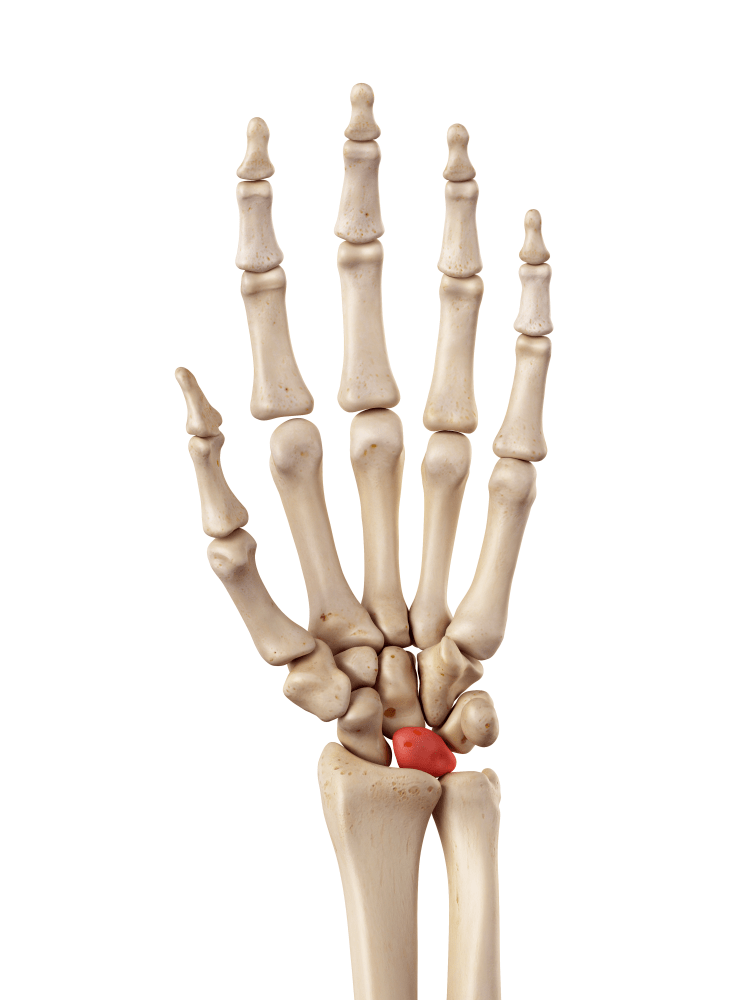

Where is the lunate bone?

The lunate bone is one of 8 bones which make up the wrist joint, and is situated right at the centre of the wrist.